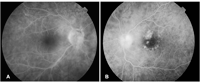

Figura 4). El disco óptico estaba repleto y bien delimitado sin borramiento en el OD, mientras que había elevación, borrosidad y congestión en el OI. La mácula en dicho ojo presentaba una zona de fibrosis temporal, sin evidencia de fluido subretiniano. No se observaron signos de retinopatía diabética, pero sí una discreta turbidez vítrea bilateral. La angiografía fluoresceínica mostró fuga tardía de contraste en papila izquierda, discreto parcheado coroideo y en el ojo derecho, discreto envainamiento temporal inferior, sin clara evidencia de fuga. No había signos de edema macular u otros cambios (

Figura 5).

Figura 5A y 5B. Imágenes de angiografía fluorosceínica al momento del diagnóstico. Figura 5A. Ojo derecho muestra envainamiento vascular temporal inferior sin signos claros de fuga. Figura 5B. En ojo izquierdo, se objetiva parcheado coroideo irregular, fuga a nivel papilar y zonas de cicatrización a nivel macular, correspondientes a terapia fotodinámica antigua.

La angiografía fluoresceínica (AF) puede ser útil en identificar el edema macular quístico y la vasculitis retiniana, con hiperfluorescencia parcheada, característica de la afectación de pequeño vaso, así como los episodios de papilitis, como en el caso ilustrado. La fuga de vasos retinianos puede preceder a la aparición de las lesiones características en el fondo de ojo. En estadios avanzados, se objetiva atenuación vascular y atrofia coriorretiniana y de nervio óptico.